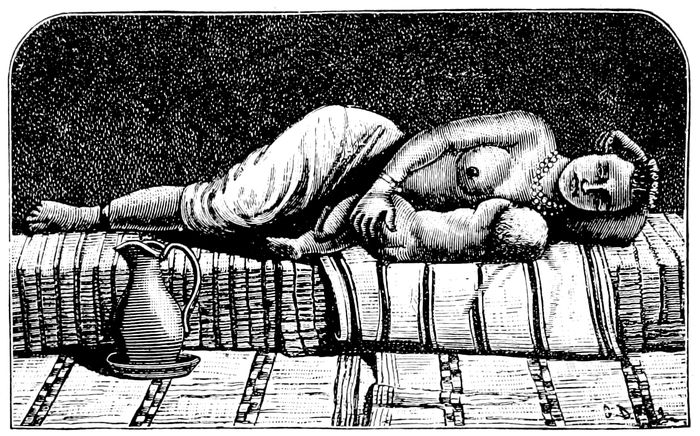

Delivery in side position |

141 |